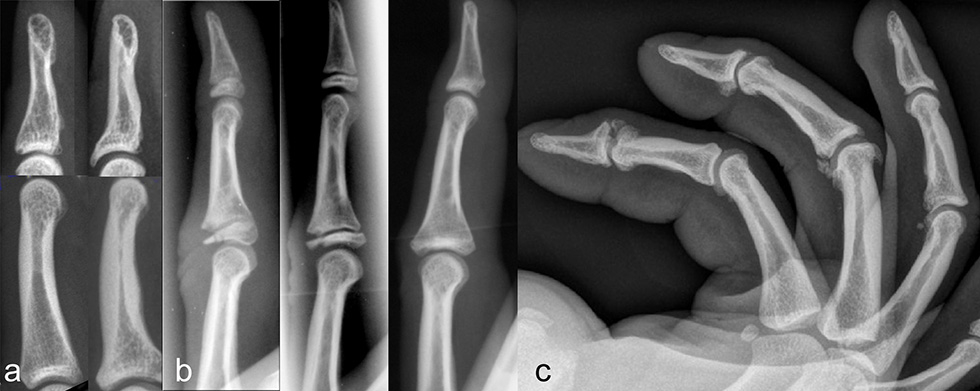

Figure 3

Osseous adaptations of climber’s distal and middle phalanx compared with a non-climbers bones (A); epiphyseal thinning (B, left), epiphyseal fracture (B, middle) in an adolescent climber, strict avoidance of crimp grip let the fracture heal without a joint surface incongruity or axial deviation (B, right); lateral view of the fingers of a 38-year-old world class boulderer, almost every joint shows osteophytes and calcifications of the capsule, joint space narrowing, a main sign of osteoarthritis however is not apparent.

Climbing of particularly difficult routes with small holds leads to very high impact-forces on the finger bones and joints with impressive changes of the thickness of the cortices (fig. 3) [32]. Whether rock-climbing leads also to a degenerative arthritis of the finger joint has already been debated and investigated by different authors [33–35]. They described radiographical changes of finger joints of long-term climbers such as osteophytes, subchondral sclerosis and joint space narrowing. Nevertheless, none of those authors could show clear evidence of an increased rate of degenerative arthritis compared to an age-matched group of non-climbers [33–35]. In these studies the radiographs were mostly performed in an anterior-posterior view and the changes of the joints were assessed according to the Kellgren and Lawrence [36] or the Altmann score [37]. We conducted a study [38] where we investigated the anterior-posterior and the lateral views of the fingers in a group of 31 Swiss performance sport climbers. The mean of years of climbing was 20 years and the mean of the highest reached sport climbing level was 8b redpoint (French grade, corresponding to UIAA grade 10). Almost all of the climbers had little or no symptoms in the finger joints but up to 84% showed osteophytes at the PIP-joints and up to 68% in the DIP-joints. According to the Kellgren and Lawrence score 6 climbers (19%) had signs of an osteoarthritis (significant) whereas the age-matched non-climbing-group had practically no signs of radiological changes in the finger joints. We observed that in the lateral views (fig. 3) the climbers showed even more impressive osteophytes in the DIP and PIP joints. However there were almost no other apparent changes such as subchondral cysts, osteolysis or joint space narrowing. Most of the climbers concerned had performed bouldering at a high level and were older than 35 years. These climbers reported rare episodes of slight pain and stiffness on the dorsal side of the joints when hitting hard objects or after climbing intensively with the crimp-grip-position. This can be explained by an irritation of the dorsal side of the joint capsule by the osteopytes [39]. The pain usually disappears after 3–5 weeks, sometimes corticosteroid-injections are necessary and very rarely such an osteophyte has to be removed. Even when calcified parts or osteophytes are broken off and freely move in the joint, they are taken up by the joint capsule and become asymptomatic after several weeks.

Particularly in young adolescent climbers or in children, the full crimp-grip-position has to be avoided. The growth plates of the finger bones are not closed until the age of 17–19 years, are the weakest structures of the finger, and are most susceptible to injuries [42, 43]. In the full crimp-grip-position a shift of the middle phalanx results in a very high load proximal to the dorsal part of the base of the middle-phalanx. This may lead to growth-plate overload, consolidation and partial necrosis and finally to growth plate fracture (Salter-Harris II fracture, fig. 3). Premature partial or complete closure of the growth-plate with uneven or interrupted further growth of the finger bone ending up in a considerable axial-deviation or foreshortened finger may follow. Even complete destruction of the joints and early degenerative changes are possible. As soon as pain without obvious trauma in the PIP-joints is apparent in an adolescent, the crimp-grip-position should not be tolerated at all until the pain disappears or the growth-plates have closed at the age of 17–19 years. Regular radiographic controls are mandatory.